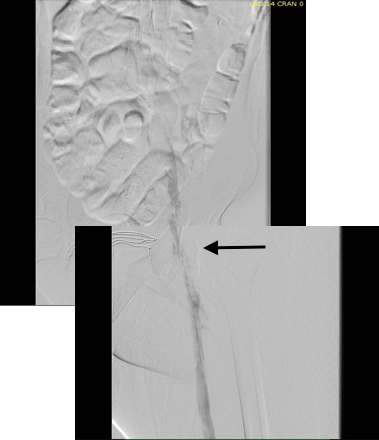

Once the wire crossed into the iliac vein from above, it was captured and brought out. While ballooning by itself is inadequate for revascularization, it greatly eases wire capture and on the right, it was done simply by driving the wire from above into the sheath. Wire capture wins access across the iliocaval and IVC filter occlusion from below.

intervention fig 3.png

Wire passage across IVC filter into right and left systems

Once wire access is done, ballooning across the filter is done from both sides. A large sheath is them delivered across the IVC filter. Finally, a Palmaz stent mounted on a large balloon is delivered and deployed. I chose to do this from the right access, and retracted the wire on the left -something done with some trepidation because of the great difficulty gaining this access, but with with prior balloon dilatation, reaccess is made easier. Also, plan B would be reaccess from above.

intervention fig 4.png

After balloon dilatation of occlusion typically to 8mm from both sides, a sheath placed and Palmaz stent deployed across filter on a large 24mm balloon

When this is accomplished, the left sided wire is reaccessed across this stent. This is the venous side analogue to gate access in EVAR (below).

intervention fig 5.png

Reaccess of the left iliac venous wire across Palmaz stent

Once this is done, the iliac veins are dilated to 14mm from the IVC to the common femoral arteries. large 18mm Wall stents are deployed in a kissing fashion from the caval stent into both iliac systems and dilated to 18mm.

intervention fig 6.png

Predilatation of iliac venous systems with ever larger balloons, deployement of bilateral 18mm Wall Stents

After deployment, the Wall Stents are ballooned to 18mm. These stents were extended into the common femoral artery with 14mm nitinol stents.

intervention fig 7.png

Ballooning 18 mm Wall Stents with 18mm Atlas balloons, then extending to CFA with nitinol stents of 14mm